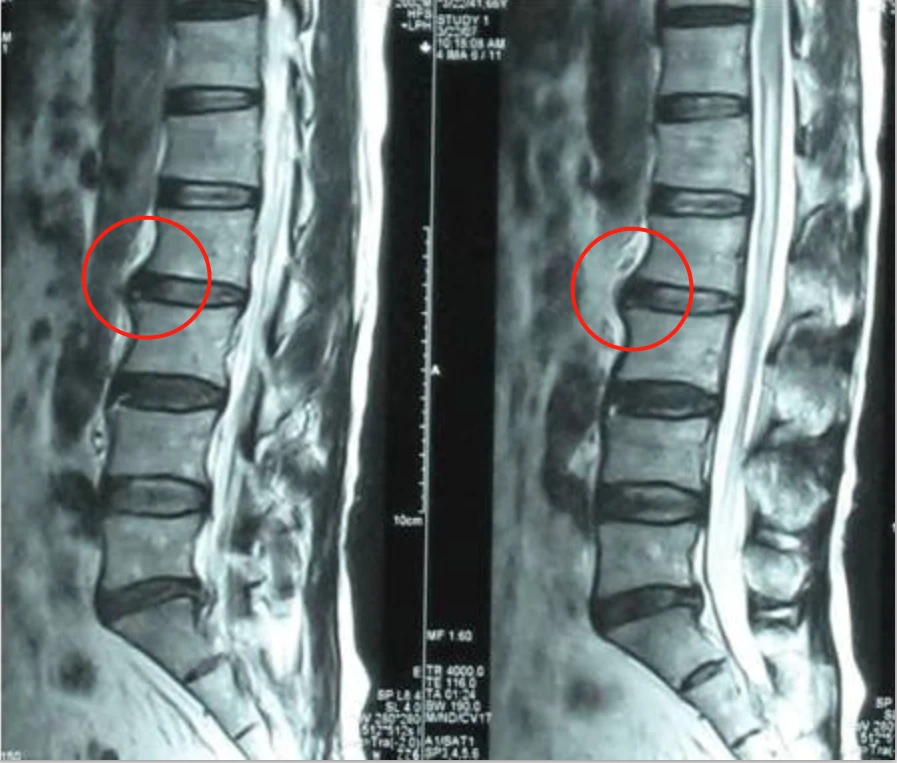

3.什么是腰椎间盘突出症?

腰椎间盘突出症是临床上较为常见的腰部疾患之一,发病原因主要在于腰椎间盘的退行性变化、外伤和劳损等,致使作为椎间盘主要支架的纤维环变得薄弱、甚至破裂。纤维环薄弱或破裂多位于椎间盘后方或侧后方。腰椎间盘向后方的椎管内突出,或破裂脱出,导致相邻的组织,如脊神经根、脊髓等遭受刺激或压迫,从而产生腰部疼痛、单侧或双侧下肢麻木、疼痛等临床症状。

1、由于椎间盘是人体内最大的无血管组织,主要是靠软骨板的渗透提供营养的,现有药物大多需经肠胃吸收血液循环才能到达病变部位,因而疗效甚微。患者常常看到,通过X光片、CT、磁共振,自己的病情被诊断得清清楚楚,但是治来治去就是治不好。

2、椎间盘突出日久易钙化、粘连,而椎间盘突出后椎间隙变窄,椎体受到不正常牵拉,必然引发骨质增生、产生无茵性炎症。手术只是解决了突出物压迫神经的问题,而对于椎间盘突出引起的钙化粘连等继发症,却无能为力。很多患者虽然做了手术,甚至做了两三次手术,CT、磁共振已明确显示突出物消失,神经受压解除,而病情却没有多大好转,就是这个原因。